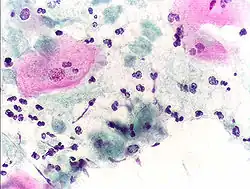

Micrograph of a normal pap smear -

Micrograph of a Pap test showing a low-grade intraepithelial lesion (LSIL) and benign endocervical mucosa. Pap stain. -

Micrograph of a Pap test showing trichomoniasis. Trichomonas organism seen in the upper right. Pap stain. -

Endocervical adenocarcinoma on a pap test. -

Candida organisms on a pap test. -

Viral cytopathic effect consistent with herpes simplex virus on a pap test. -

Normal squamous epithelial cells in premenopausal women -

Atrophic squamous cells in postmenopausal women

Normal endocervical cells should be present into the slide, as a proof of a good quality sampling

The cytoplasms of squamous epithelial cells melted out; many Döderlein bacilli can be seen.

Infestation by Trichomonas vaginalis

An obviously atypical cell can be seen